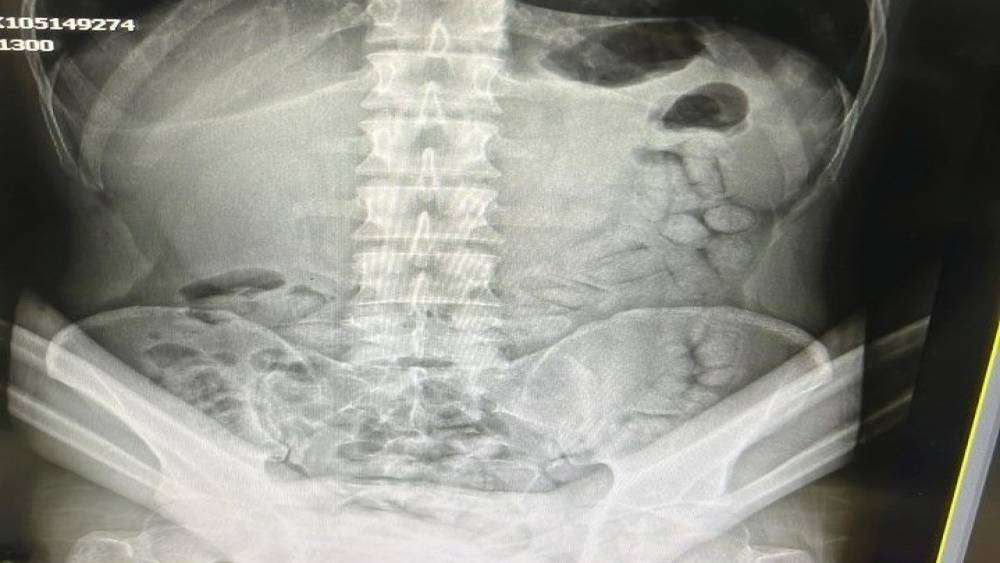

Gümüşhane’de polis ekiplerinin kontrol noktasında durdurduğu araç içerisindeki İran uyruklu şahsın bağırsaklarından 55 adet kapsül halinde metamfetamin ele geçirildi.

Edinilen bilgilere göre, Gümüşhane İl Emniyet Müdürlüğü’ne bağlı Narkotik Suçlarla Mücadele Şube Müdürlüğü ekipleri yaptıkları istihbarat çalışmaları neticesinde uyuşturucu kuryesi olduğu tespit edilen İran uyruklu S.R.N. isimli şahsı Akçakale Uygulama Noktasında yakalayarak gözaltına aldı. Adli makamların talimatı üzerine Gümüşhane Devlet Hastanesine götürülen şahsa yönelik iç beden muayenesinde bağırsaklarında 55 adet kapsül olduğu tespit edildi. Hastanede yapılan müdahalenin ardından şahsın bağırsaklarından çıkarılan kapsüllerin içerisinde toplamda 317,46 gram metamfetamin ele geçirildi. Hakkında Uyuşturucu Madde Nakli suçundan işlem başlatılan yabancı uyruklu şahıs yasal işlemlerinin tamamlanmasının ardından çıkarıldığı mahkemece tutuklanarak Gümüşhane E Tipi Kapalı Ceza İnfaz Kurumuna gönderildi.

Adli makamların talimatı üzerine Gümüşhane Devlet Hastanesine götürülen şahsa yönelik iç beden muayenesinde bağırsaklarında 55 adet kapsül olduğu tespit edildi. Hastanede yapılan müdahalenin ardından şahsın bağırsaklarından çıkarılan kapsüllerin içerisinde toplamda 317,46 gram metamfetamin ele geçirildi.